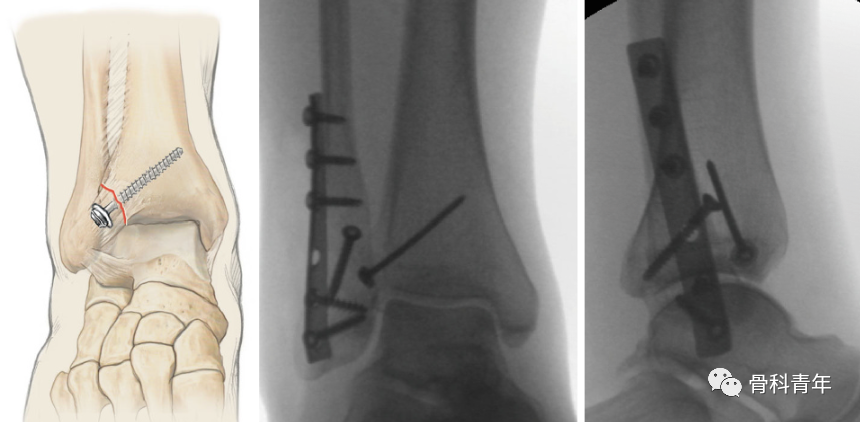

也有学者采用锚钉固定,将骨块通过锚钉缝线固定于胫骨远端,但该方法的总体固定强度不如内固定。考虑到张力带原则在腱-骨连接处骨折中的广泛应用,如髌骨、内踝等,有研究人员开始采用克氏针张力带技术固定Chaput骨块:

步骤1:前外侧切口暴露Chaput结节,小复位钳临时复位,根据Chaput骨块的大小,平行穿入两枚1.2-1.6mm克氏针,固定至胫骨远端。

步骤2:距骨折线3cm的胫骨远端,置入一枚4mm松质骨螺钉,绕螺钉即克氏针尾部,0.8mm钢丝“8”字固定。

该固定方法并非对所有Chaput骨折均适用,需要骨块较为完整;在固定过程中,前外侧切口暴露Chaput骨块较为清楚,间隔3cm置入松质骨螺钉可能较为困难,显露不够,必要时可能需要另外切口,增加手术创伤。对骨块较小且完整,螺钉固定易致骨块碎裂者,此方法可能较为适用。